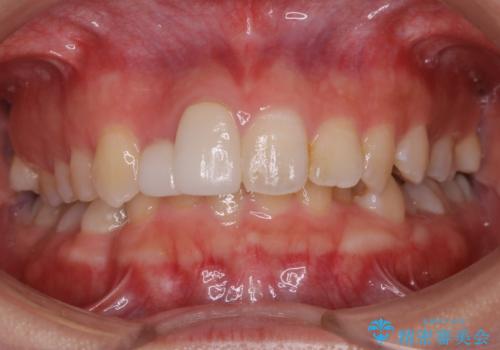

- 歯のガタつき、顎のズレ、出っ歯を気にして来院された患者様です。

歯を抜きたくないとの希望であったためマウスピース治療をお勧めしましたが、

マウスピースをずっとつけていることは難しいとの事であったためワイヤー矯正治療を行うこととなりました。

インビザラインの方法でも治せる患者様でしたが、希望によりワイヤー矯正となりました。